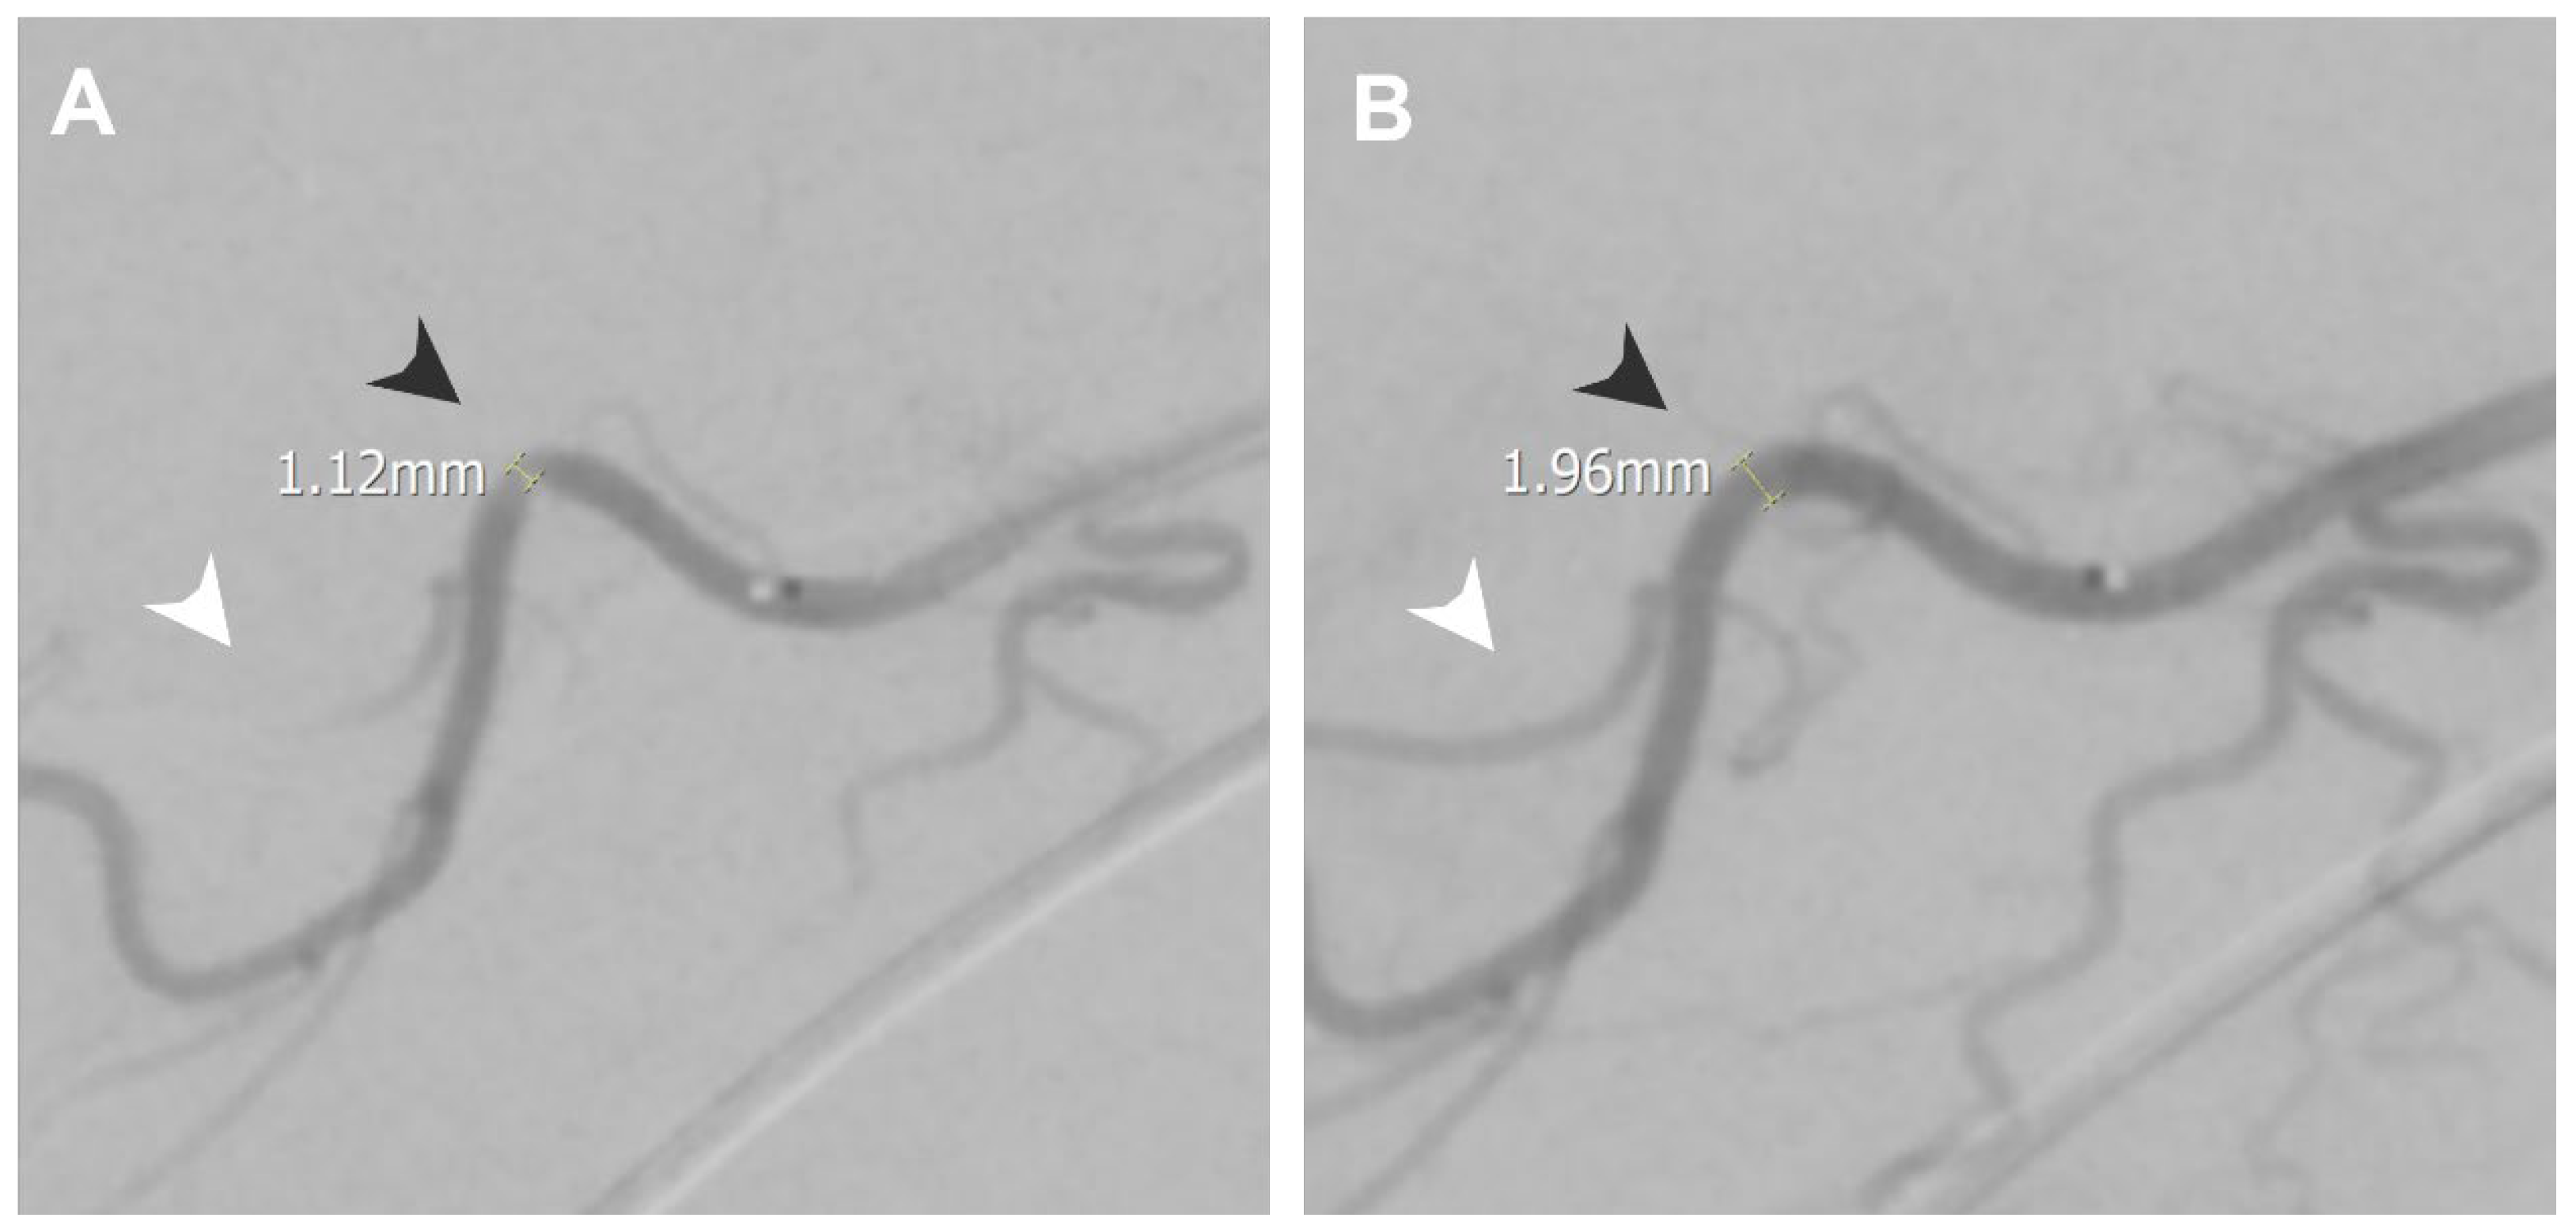

| Secondary stiff shoulder | Thoracoacromial artery | 1.12 | 1.96 |